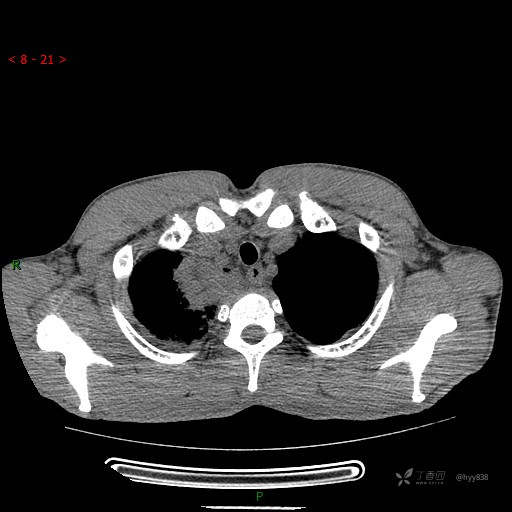

增强动脉期